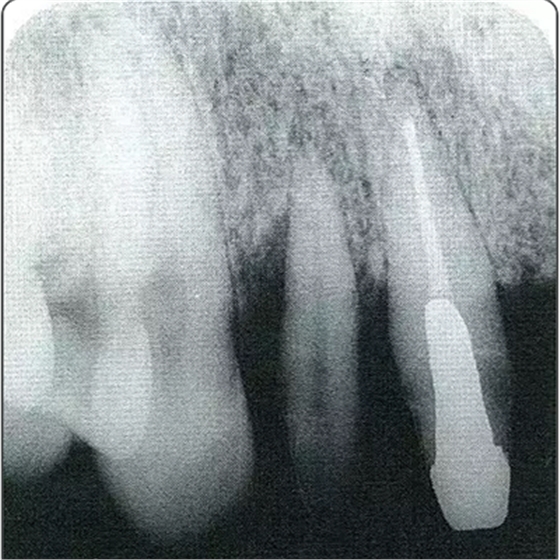

圖10-2 x片顯示的遠(yuǎn)中部有垂直性骨缺損。